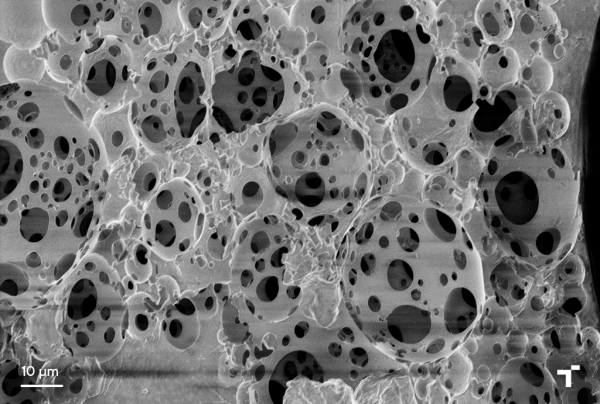

Además de coordinar el proyecto, el centro tecnológico ha focalizado su actividad en el desarrollo de tecnologías integradas en las áreas de especialización de ingeniera de superficies y fabricación avanzada del centro, como el procesado de polímeros a escala micrométrica, con el propósito de optimizar la estructura tubular (compuesta por microcanales) del implante, mimetizando la geometría del nervio nativo.

El centro vasco también ha trabajado con polímeros sintéticos y naturales sintetizados por otros socios del consorcio, así como mezclas de ambos, y ha adecuado las tecnologías de microfabricación a las propiedades biofísicas de los nuevos materiales.